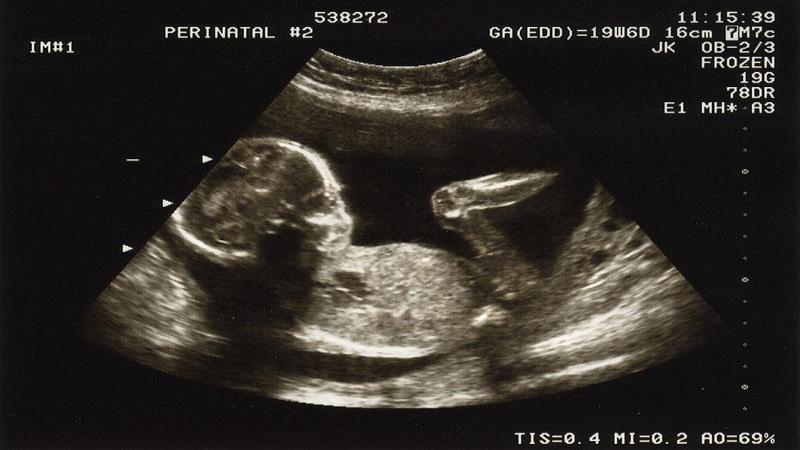

در اوایل بارداری می توان از سونوگرافی برای تعیین باردار بودن بیمار و تعیین سن بارداری دقیق استفاده کرد. سن حاملگی دقیق بسیار مهم است زیرا تصمیم گیری در مورد بارداری بعد از 20 هفته بر اساس هفته حاملگی تعیین می شود. سونوگرافی های قبلی تاریخ دقیق تری به ما می دهند.

سن و جنسیت کودک خود را تعیین کنید: سونوگرافی جزئیات مهمی را به ما می گوید که به ما کمک می کند تا تاریخ زایمان خود را تعیین کنیم و شما شروع به انتخاب لباس برای کودک کنید.